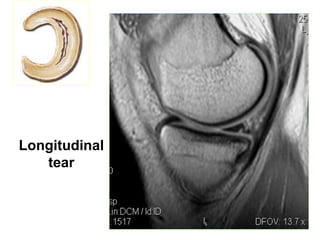

o Longitudinal tear

Longitudinal

tear